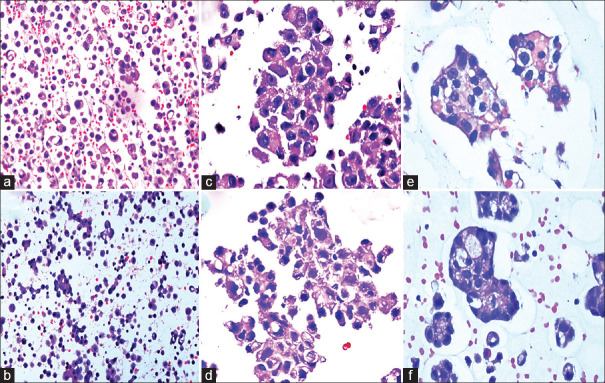

Material and methods: Two sets of agar-embedded CBs were processed from 50 effusion samples. CBs were further processed by conventional and rapid methods. Conventional CBs (CCB) were processed in a histoprocessor, whereas rapid CB was processed in a heated water bath with an agitation facility. For HICB processing, dehydration and clearing were performed at 50°C followed by paraffin wax impregnation at 65°C temperature. From both CBs, sections of 5 um thickness were cut and stained with hematoxylin and eosin (H and E). Cell morphology, cost, and time were compared between the two methods. The feasibility of IHC was attempted in a few cases.

Results: HICB was completed within 4.30 h compared with CCB. Diagnoses on both CBs were concordant in all the cases. Incomplete dehydration was noted in six (12%) cases, but the diagnosis was not compromised. No additional cost was involved in HICB. On IHC, both HICB and CCB exhibited equivalent expression.